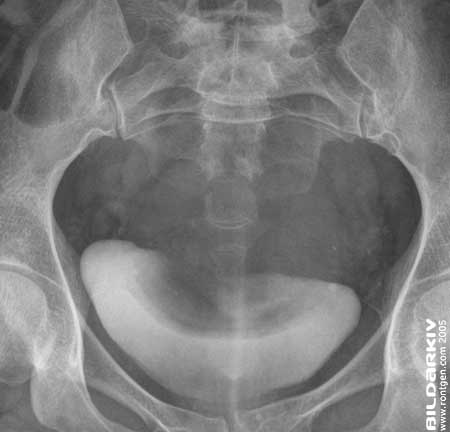

Urografi 8

Vinklad projektion av urinblåsan 20 minuter efter kontrastmedelsinjektion.